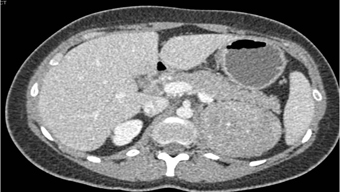

In this patient with symptoms of Cushings Disease the best diagnosis is?

adrenal adenoma

pheochromocytoma

lymphoma

primary adrenal carcinoma